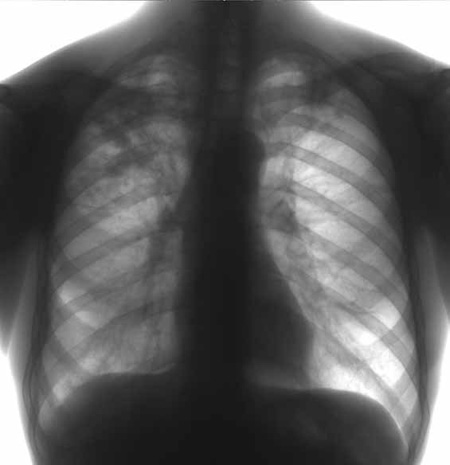

Это вид туберкулеза, проявляющийся острым воспалением легкого. Развитие заболевания происходит при повторном инфицировании заживающих участков легкого.